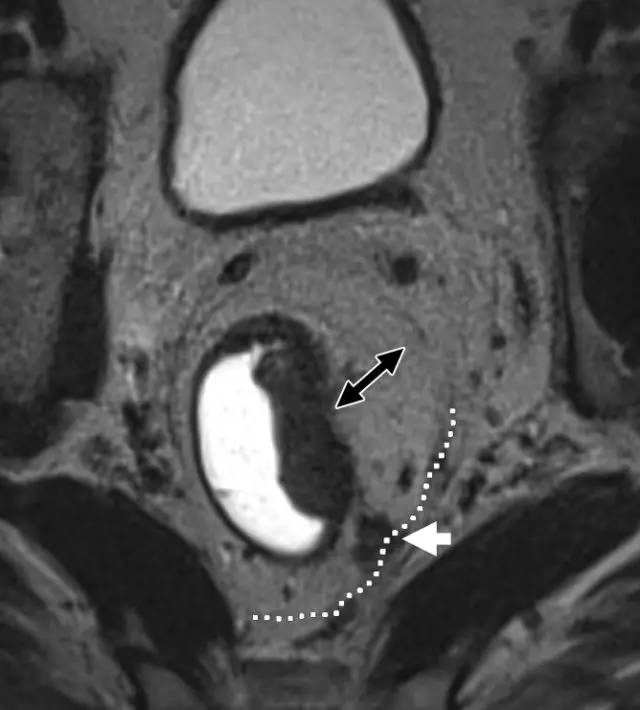

图 29 轴向 T2 加权图像报告 CRM 的距离。虚线描绘了直肠系膜筋膜,这是 T3a 肿瘤的 CRM,预测 CRM 阴性

图 30 轴向 T2 加权图像报告 CRM 的距离。T3a 肿瘤远离直肠系膜筋膜(黑色箭头),但直肠系膜筋膜上的可疑淋巴结(白色箭头)提高了 CRM 阳性(CRM = 0 mm)的可能性。